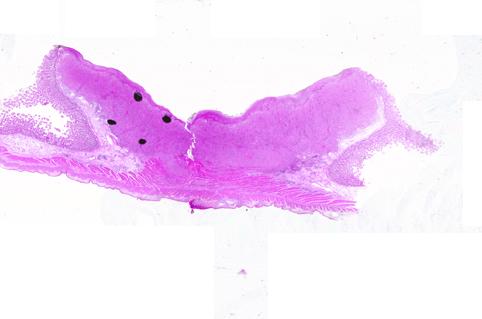

질환(병리주체)의 분류 전이성종양/

부위(장기별) 소장/공장

검사방법 마이크로

종양의 육안분류 2형(궤양국한형)/

종양의 최대경(밀리미터) 25~29

종양의 심달도 mp

다발종양(동일 장기) 유(동시성)

다중종양(다수의 장기) 유(동시성)